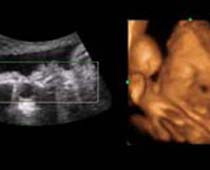

Clips vidéo 4D scan ultrason fœtal | Dr N Layyous

Clips vidéo 4D scan ultrason fœtal